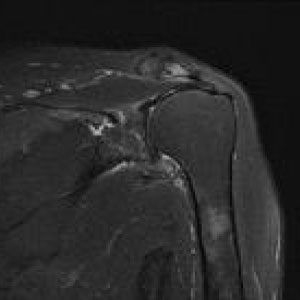

MRIはMagneticResonanceImageの略で強い磁石と電波によって人体の構造を見ることが出来る検査です。

頭部領域から脊椎・関節・骨疾患、腹部に至るまで全身部位の診断に役立ちます。

脳梗塞、脳腫瘍、脳動脈瘤、頚髄症、椎間板ヘルニア、脊柱管狭窄症、脊椎圧迫骨折、腱板損傷、各関節靭帯損傷、半月板損傷、骨壊死、肉離れ、骨腫瘍、軟部腫瘍、炎症、など